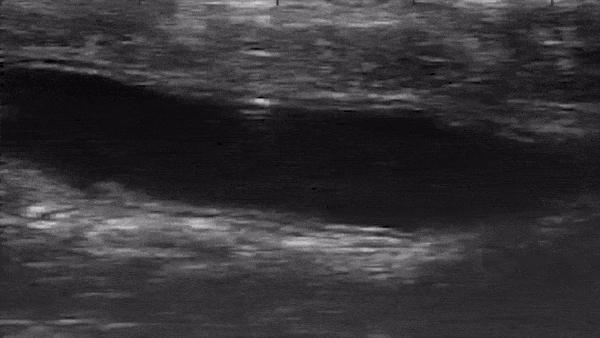

Роботы настолько малы, что разработчики смогли протиснуть их через анусы в кишечник живых мышей. С помощью ультразвукового зонда они смогли увидеть, как роботы двигаются через кишечник, и обнаружили, что микроприборы хорошо реагируют на наведение магнитного поля. То же самое было опробовано в вырезанном кишечнике свиней с похожими результатами.